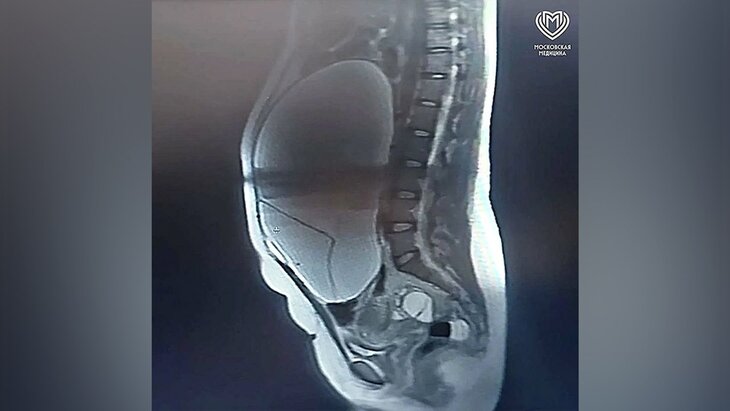

Женщина поступила в медучреждение с доброкачественным новообразованием яичника 35×35 сантиметров. Опухоль привела к развитию илеофеморального тромбоза протяженностью 25 сантиметров – состояния, которое создавало прямую угрозу для жизни пациентки.